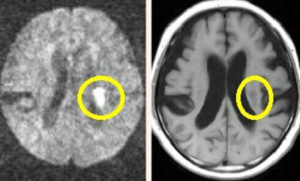

病気【脳・神経系】 脳梗塞(のうこうそく)とは? 症状や治療、リハビリ方法、予防するには? 2019年11月20日 こんにちは、ふみーずステディです。 東京都江戸川区にて現役在宅ケアマネージャーとして単独居宅支援事業にて勤務しております。 日本人の死因の上位を占める三大疾病をご存じでしょうか? 三大疾病とは、①【がん(悪性新生物)】②【急性心筋梗塞】③【脳卒中】の3つの病気を指します。 これらの病気は、長く日本人の死因の上位を... ふみーずステディ